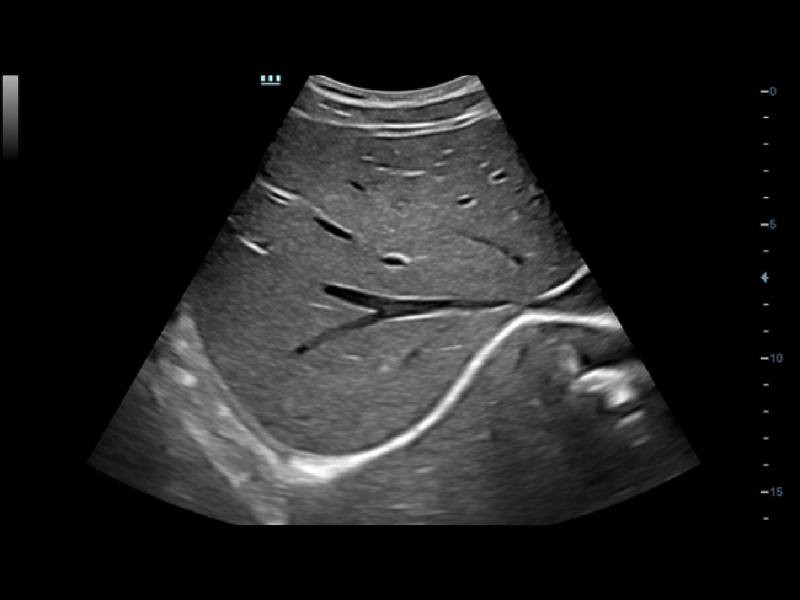

Em combinação com a exclusiva tecnologia 3T da Mindray (combinação de três camadas, design de corte total, controle térmico), os otimizados transdutores convexos, com feixe em fases e volume oferecem uma cobertura de aplicação mais extensa, resultando em uma excelente solução de varredura nas áreas de ABD, cardiologia, obstetrícia/ginecologia, entre outras.